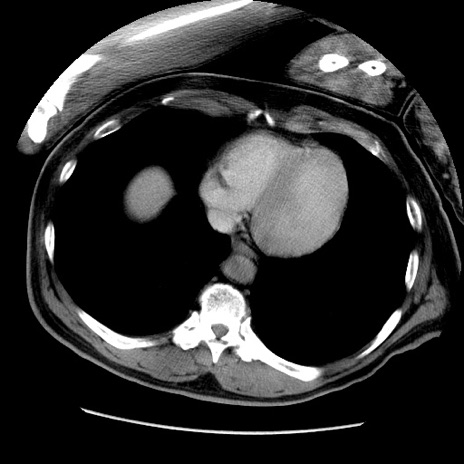

症例22(横断像)

【症例】50歳代男性

【主訴】腹痛

【現病歴】AVMからの被殻出血のため回復期リハ病棟入院中。 本日午後3時頃急に下腹部痛が出現した。

【既往歴】AVM、被殻出血、虫垂炎、高血圧

【身体所見】意識晴明、左半身不全麻痺、会話の理解は良好、36.5°C、腹部:膨隆、全体に板状硬、下腹部正中に圧痛点あり、反跳痛-、筋性防御不明、右下腹部にope scar

【データ】WBC 9400、CRP 0.06